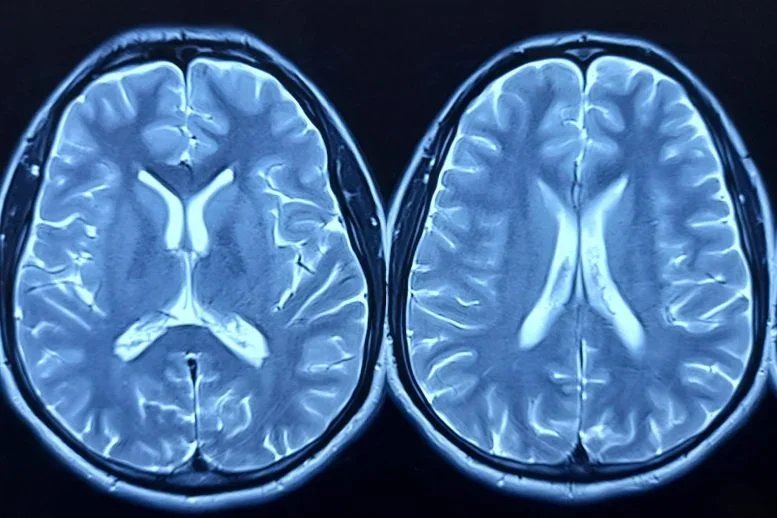

لقد استكشفت الأبحاث كيف يختلف التعبير الجيني (قياس كمية البروتين المشفر بواسطة الجين) بين أنسجة المخ لدى الأشخاص المصابين بمرض الزهايمر وأولئك الذين لا يعانون من المرض، وغالبًا ما يكون ذلك في EA أو مجموعات ذات أسلاف مختلطة. ومع ذلك، فإن العديد من هذه الدراسات شملت عددًا قليلاً جدًا من المشاركين في AA، أو لم تحدد أعدادهم، مما يجعل من الصعب اكتشاف أنماط ذات معنى خاصة بهذه المجموعة.

في أكبر دراسة من نوعها باستخدام أنسجة المخ من متبرعين بـ AA، حدد العلماء في كلية الطب تشوبانيان وأفيديسيان بجامعة بوسطن العديد من الجينات التي تختلف مستويات نشاطها بين حالات مرض الزهايمر والضوابط. لم يتم ربط العديد من هذه الجينات سابقًا بمرض الزهايمر من خلال الأبحاث الجينية الأخرى. وكانت النتيجة الأكثر إثارة للدهشة هي زيادة بمقدار 1.5 مرة في التعبير عن جين ADAMTS2 في أنسجة المخ لدى الأفراد الذين تم تأكيد تشريح الجثث لديهم.

لإجراء التحليل، قام الفريق بجمع عينات من قشرة الفص الجبهي بعد الوفاة من 207 متبرعين بالدماغ من خلال 14 مركزًا لأبحاث AD الممولة من المعاهد الوطنية للصحة في جميع أنحاء البلاد. ضمت هذه المجموعة 125 متبرعًا مصابًا بمرض الزهايمر المؤكد مرضيًا و82 مجموعة تحكم. ظهر ADAMTS2 باعتباره الجين الأكثر تغيرًا وتم تصنيفه أيضًا أعلى في دراسة منفصلة بقيادة نفس الباحثين الذين قاموا بتحليل أنسجة المخ من مجموعة EA أكبر بكثير. في هذا العمل، تمت مقارنة التعبير الجيني بين الأشخاص المصابين بمرض الزهايمر المؤكد والذين أظهروا أعراضًا معرفية قبل الوفاة وأولئك الذين يعانون من أمراض دماغية مماثلة والذين ظلوا مرنين إدراكيًا.